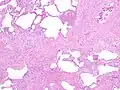

The histologic hallmarks of UIP, as seen in lung tissue under a microscope by a pathologist, are interstitial fibrosis in a "patchwork pattern", honeycomb change and fibroblast foci (see images below).[6][7]

Appearance of honeycomb change in a surgical lung biopsy at low magnification. The dilated spaces seen here are filled with mucin. Hematoxylin-eosin stain, low magnification.